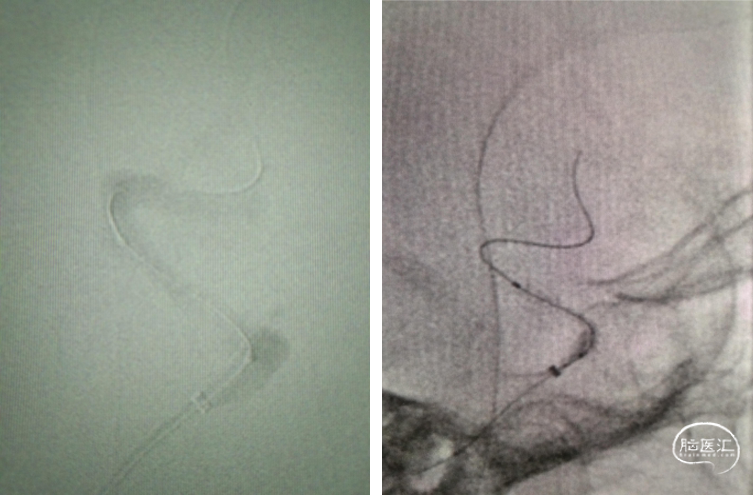

导引导管到位,微导丝通过病变

球囊覆盖病变

重要操作简述:透视下缓慢球扩压力达到6ATM(并多个角度观察);病变段形态和有无造影剂外渗。

球囊扩张

扩张后造影

重要操作简述:支架定位和防止微导丝移位;防止支架移位,缓慢释放支架,压力6ATM。

支架覆盖病变

支架释放